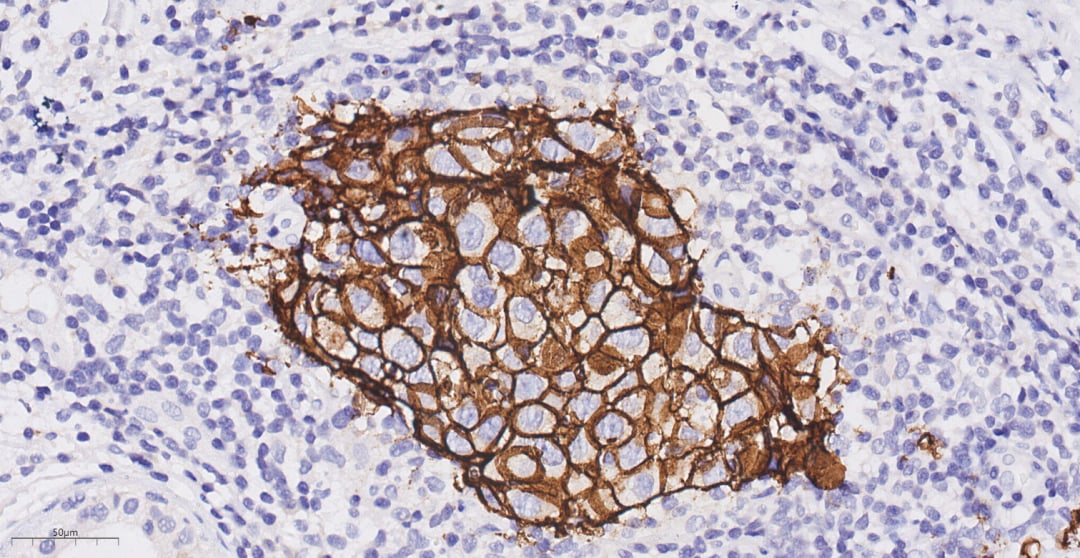

图3 癌细胞呈实性片状,间质富含淋巴细胞

图4 免疫组化显示HER2为强阳性(3+)